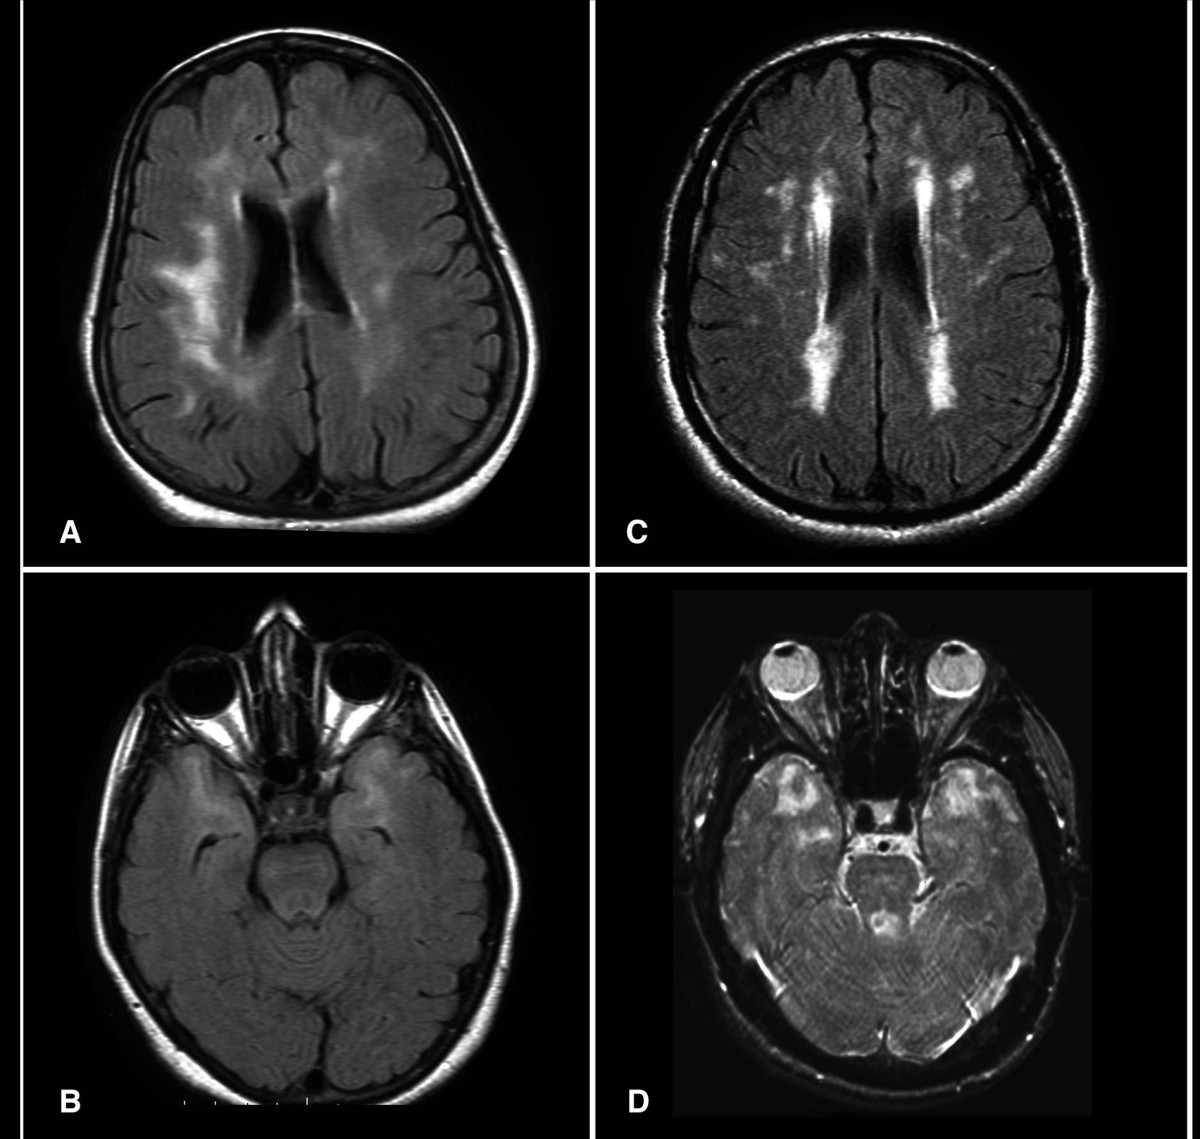

Four-panel brain MRI from patients with CADASIL. Panels a, b, and c are axial FLAIR sequences; panel d is axial T2-weighted. All four panels show confluent white matter hyperintensities in the periventricular and deep white matter, with temporal lobe involvement visible in panels a and b. Panel d additionally shows lacunar infarcts in the thalamus, pons, and basal ganglia.

Classic CADASIL imaging: axial FLAIR (a, b, c) and T2-weighted (d) MRI showing the characteristic distribution of white matter hyperintensities and lacunar infarcts. Temporal lobe involvement is visible even in the asymptomatic carrier shown in panel b. Image: Bohlega S et al., CADASIL in Arabs: clinical and genetic findings, BMC Medical Genetics 2007;8:67, CC BY 2.0, via Wikimedia Commons.